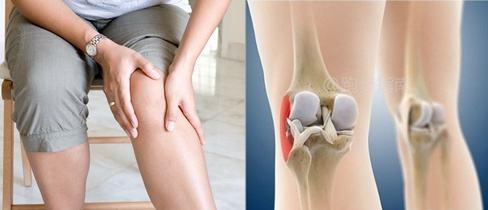

ランニング膝は典型的な症状で特徴付けられ、膝の変性や半月板の損傷とは関係なく、歩くのは問題なく、短時間走ると膝の外側付近に痛みと困難が生じ、歩行モードに切り替えると症状は治まり、走るとすぐに痛みが再発し、その結果、ランニングというスポーツに参加できなくなる、というようなものである!

膝関節の外側付近の腸脛靭帯の緊張と摩擦の主な痛点、通常は大腿骨の外側顆で、痛みのない場合もある症状のある位置ではなく、痛みの感覚にあった強さで、1日1回、1回5~7分程度マッサージしてみると、痛点がなくなり、症状が消失することがある!

ランナー膝の主な症状は、膝の前面、膝蓋骨の周囲に徐々に痛みが生じることで、長時間座っていたり、階段を上り下りしたりすると悪化する。これは、長時間座っていると大腿四頭筋が膝蓋骨を引っ張り、膝蓋骨が大腿骨に接触せざるを得なくなるためです。また、階段の上り下りや坂道の昇り降りでは、力を発揮するために大腿四頭筋をより強く収縮させる必要があるため、膝蓋骨と大腿骨表面の接触が大きくなり、痛みが悪化します。

ランニングニーランニングなどのスポーツによる膝の損傷を指す。典型的な症状は膝付近の痛みで、長時間膝を曲げて座ったり、階段を下りたり、小さな坂道を歩いたりしたときに顕著になる。ランニング中の反復運動や関節の筋肉への負担が原因です。ランニングだけでなく、ウォーキングやサイクリングなど膝を曲げる他のスポーツでもよく見られます。

「ランニング・ニー」。ランニングなどのスポーツによる膝の損傷を指す。典型的な症状は膝付近の痛みで、長時間膝を曲げて座ったり、階段を下りたり、小さな傾斜を歩いたりしたときに顕著になる。

腸脛靭帯症候群は、長距離走中または長距離走後に発症し、腸脛靭帯と大腿骨外側上顆の過度の摩擦により、靭帯または滑液包に炎症が起こる。主な症状は腫れと痛みです。